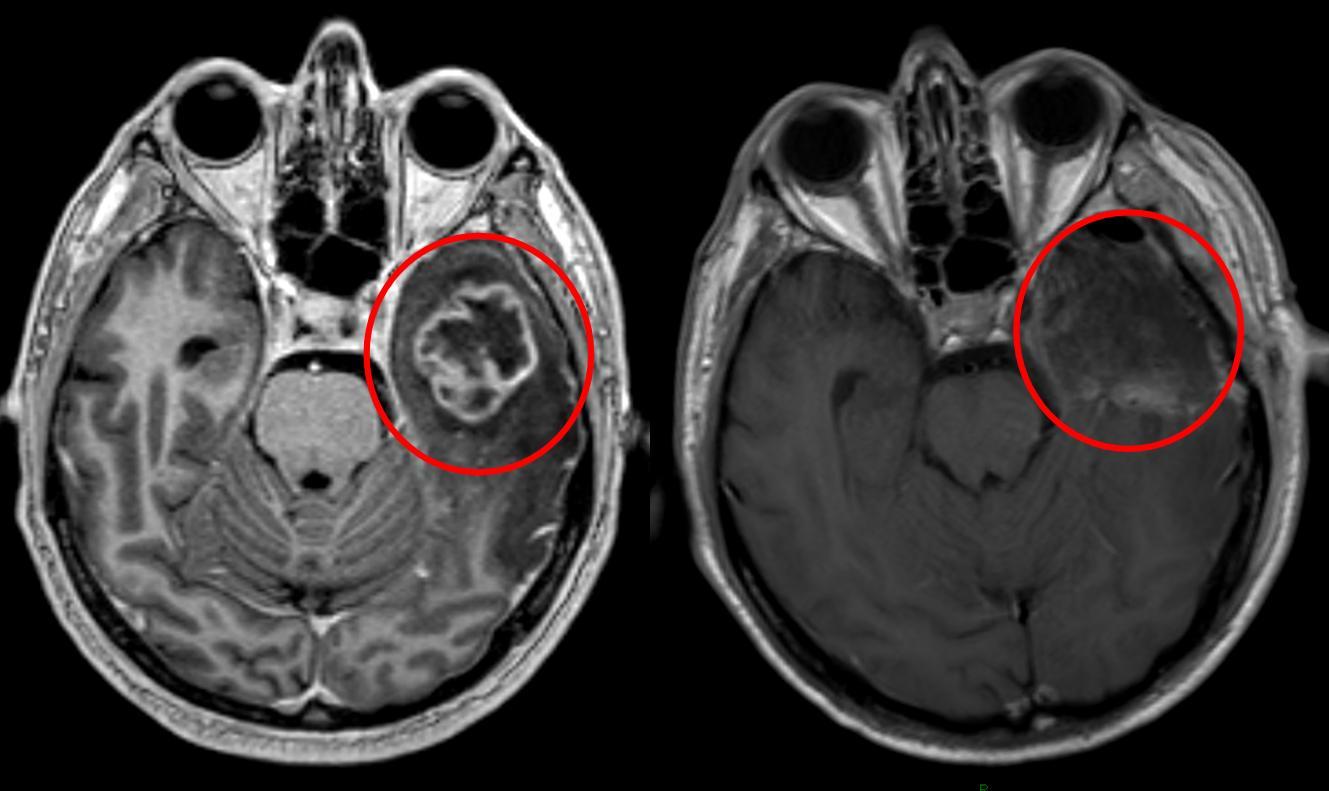

Per decenni i medici non sapevano cosa causasse questo tumore, perché non ha le mutazioni genetiche che si trovano negli altri cancri. Uno studio pubblicato ieri su Nature ha trovato una risposta inattesa: sono gli ormoni maschili. Il tumore si chiama ependimoma PFA, colpisce quasi sempre bambini sotto i cinque anni e uccide due su tre entro cinque anni dalla diagnosi. I maschi si ammalano più spesso delle femmine — e ora si sa perché. Gli androgeni, cioè il testosterone e ormoni simili, tengono le cellule tumorali in uno stato immaturo che le rende più aggressive e difficili da fermare. MedicalXpress Nei topi, bloccando questi ormoni il tumore cresce più lentamente. Farmaci che bloccano gli androgeni esistono già — si usano contro il cancro alla prostata negli adulti — ma somministrarli a neonati è un’altra cosa. Servono studi clinici appositi. Per ora i risultati sono solo in laboratorio, ma è la prima vera pista terapeutica che questo tumore abbia mai avuto.